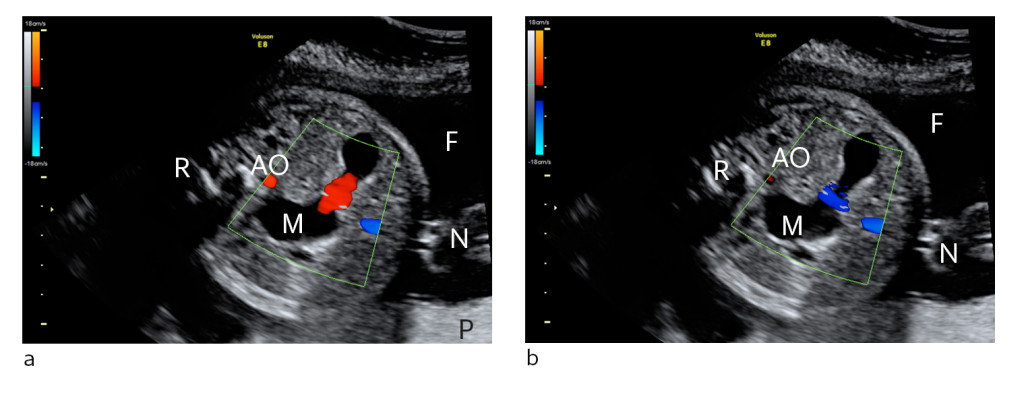

Figure 1 Ultrasound showing cross-section of fetal abdomen at gestational week 29 a) Stomach contents moving towards the…

Figure 1 Ultrasound showing cross-section of fetal abdomen at gestational week 29 a) Stomach contents moving towards the probe (red), b) Stomach contents moving away from the probe (blue). A distended stomach (M) with increased motility and movement of gastrointestinal contents back and forth is consistent with distal intestinal obstruction and reflux of contents. M = stomach. R = back, N = umbilical cord, F = amniotic fluid, P = placenta, AO = aorta abdominalis